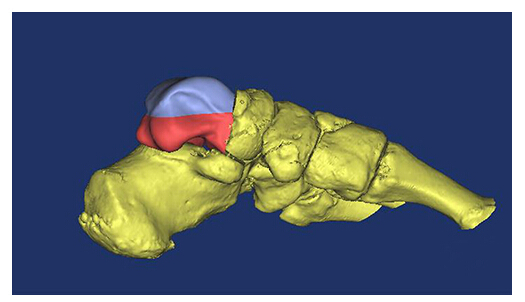

面對(duì)患者罕見的損傷,為避免距骨缺損造成的踝關(guān)節(jié)功能障礙,骨一科醫(yī)療團(tuán)隊(duì)在西安高新醫(yī)院首席專家賀西京教授的帶領(lǐng)下認(rèn)真分析病情,研究治療方案,最終決定采用目前國內(nèi)外最新技術(shù)-3D打印距骨植入恢復(fù)踝關(guān)節(jié)原有的解剖結(jié)構(gòu),恢復(fù)踝關(guān)節(jié)的屈伸功能。距骨缺失后,周圍軟組織很快發(fā)生攣縮,瘢痕組織粘連填塞其間隙,給手術(shù)治療帶來困難,前期創(chuàng)口清創(chuàng)后利用外固定架維持肢體長度保留距骨體的空間位置,為二次手術(shù)植入3D打印距骨創(chuàng)造條件。距骨形態(tài)非常特殊,在不同的方向上有多個(gè)關(guān)節(jié)面,用標(biāo)準(zhǔn)的機(jī)加工方法無法完成,采用了三維數(shù)字建模設(shè)計(jì)出該患者的距骨立體模型,根據(jù)臨床固定、功能需要采用3D打印方法制作出鈦合金人工距骨,實(shí)現(xiàn)“私人訂制”。該方案集數(shù)字化、個(gè)體化、精準(zhǔn)化制造加工技術(shù)與醫(yī)療為一體應(yīng)用于臨床,在國內(nèi)外屬領(lǐng)先技術(shù)。

此次手術(shù)植入的3D打印全距骨假體是西安高新醫(yī)院骨一科醫(yī)療團(tuán)隊(duì)根據(jù)患者的病情,利用患者自身踝關(guān)節(jié)CT數(shù)據(jù)建立患側(cè)與健側(cè)的三維數(shù)字模型,根據(jù)健側(cè)距骨數(shù)據(jù)鏡像出患側(cè)距骨三維模型。為患者“私人定制”量身定做距骨與人體完全匹配,完全個(gè)性化制作。材料使用彈性、硬度和柔韌性與人體相似的鈦合金材料,假體關(guān)節(jié)面以外采取粗糙面有很多微孔有利于骨長入、肌腱韌帶附著,維持了踝關(guān)節(jié)的穩(wěn)定。具有良好的應(yīng)用前景。